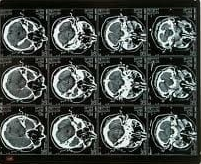

TAC CRANIO ED ENCEFALO

è un esame di imaging rapido e dettagliato che viene eseguito per visualizzare le strutture ossee del cranio e il tessuto cerebrale

- TAC Encefalo

- TAC Collo e Gola

- TAC Massiccio Facciale

- TAC Rocche e Mastoidi

- TAC Orecchio Interno

- TAC Occhio

- TAC ATM (Articolazioni Temporo-Mandibolari)